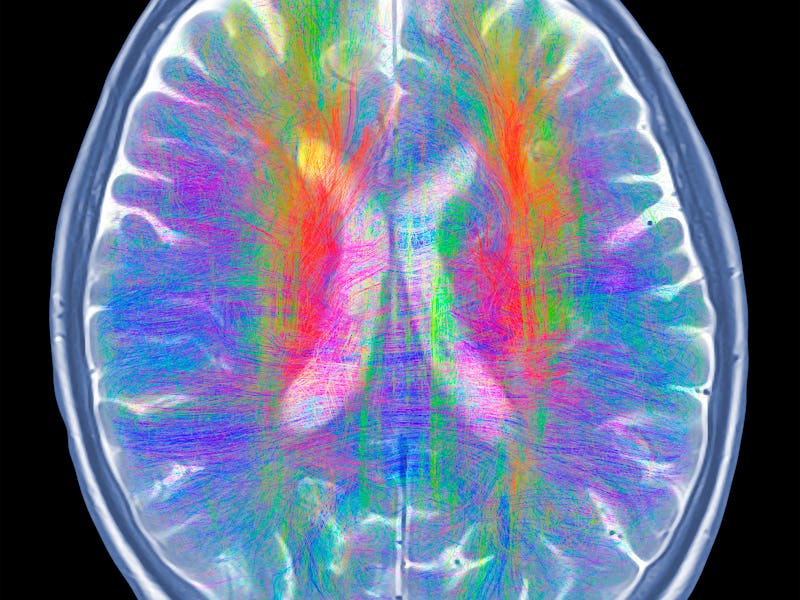

Magnetic resonance (MR) images were taken of the brain structure of the 16 participants two weeks before and two weeks after they took part in the program, which included meditation that focused on non-judgemental awareness of sensations, feelings, and the state of their mind. These brain scans revealed that the group that meditated, compared to the group that did not, had increased gray-matter density in the brain’s hippocampus and decreased gray-matter density in the amygdala.

Interestingly, the amygdala interacts with the body’s “fight-or-flight” response while the hippocampus is involved with introspection, learning, and memory.